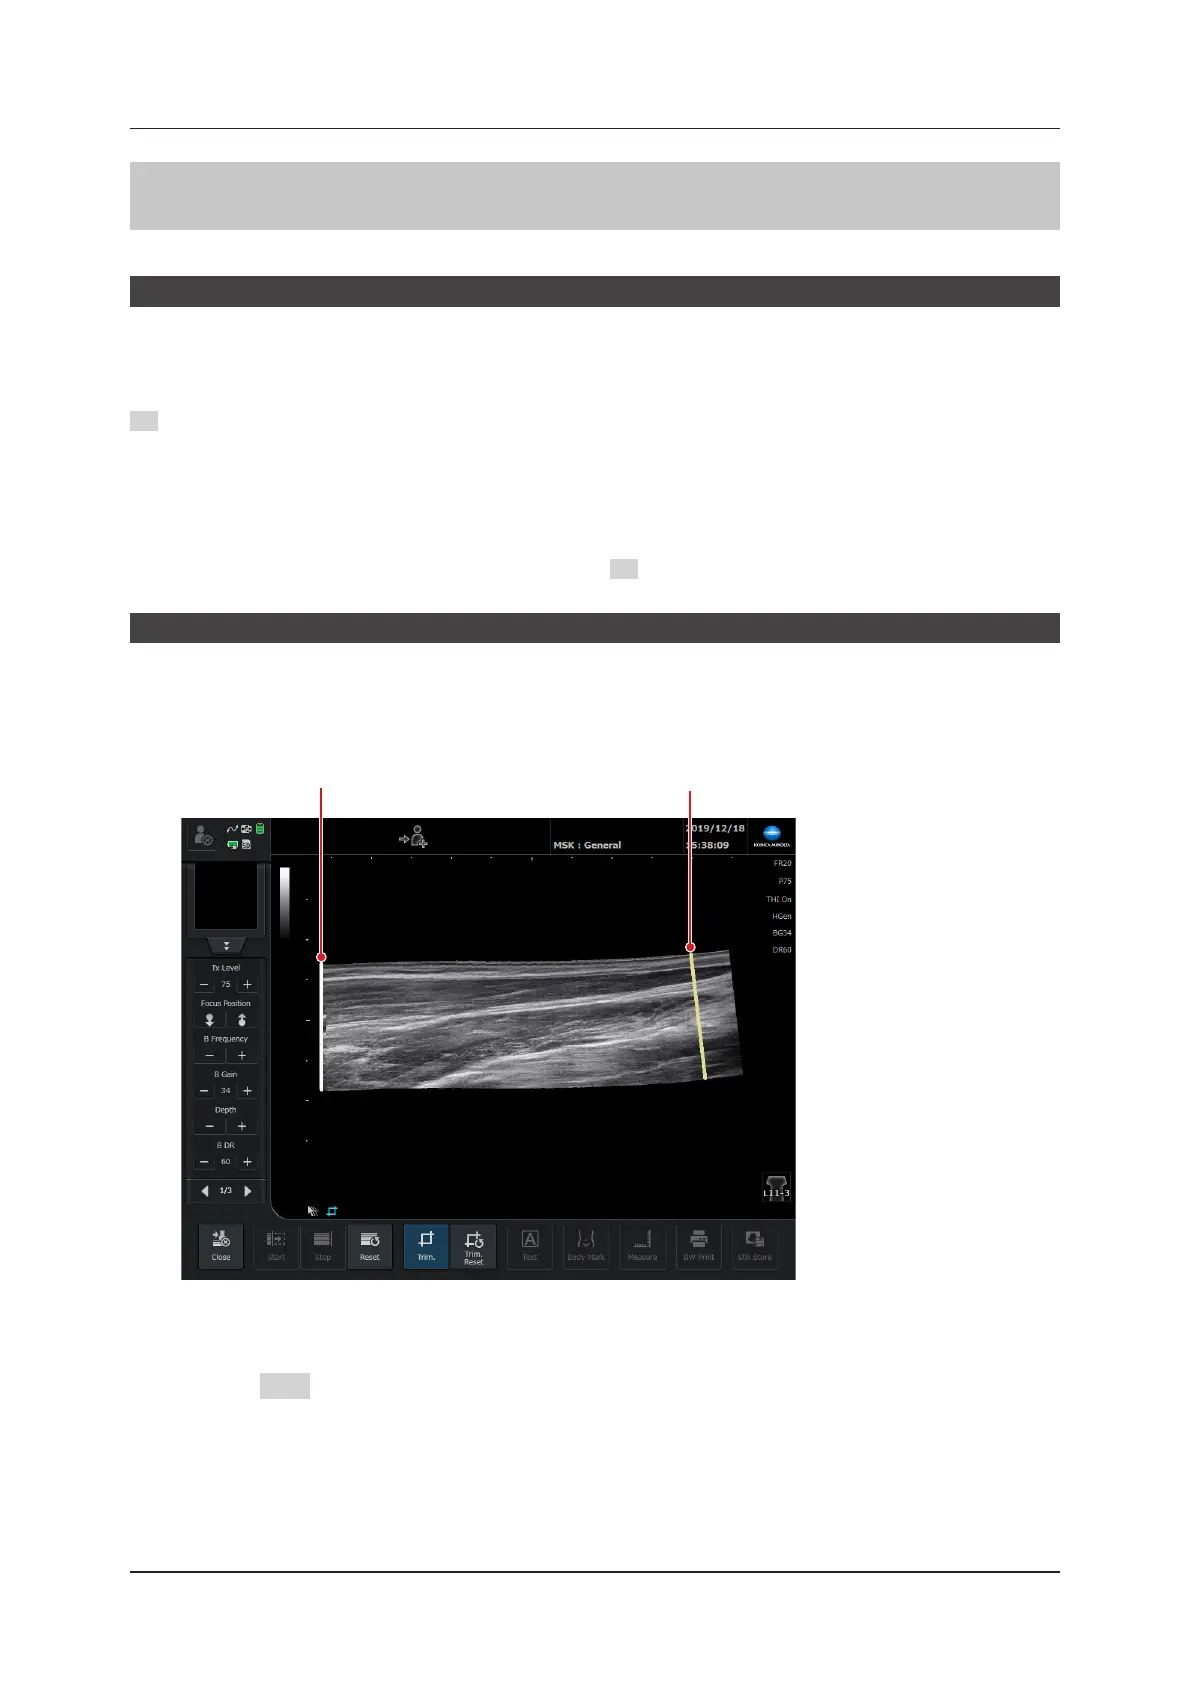

You can trim panoramic images by using the trimming function.

Press the [Trim.] button to start the trimming function.

The trimming bar appears at the start and the end of the panoramic image.

Trimming bar (start side) Trimming bar (end side)

Move the trimming bar by doing touch operations (drag) or trackball operations.

Press the SET button to x the position of the trimming bar.